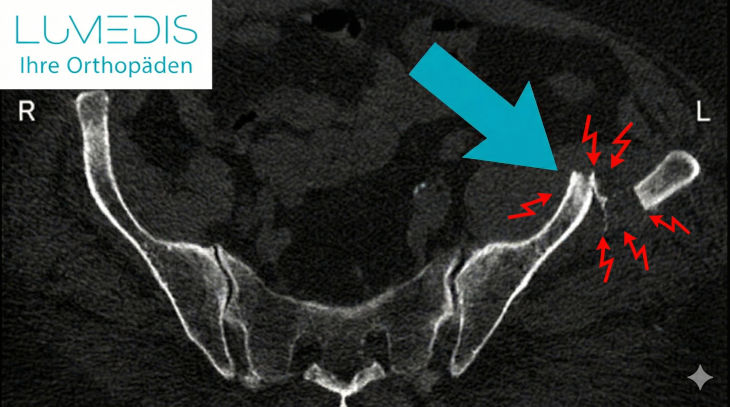

Schmerzen am ISG

CT Rekonstruktion des Beckens

Abbildung einer Sitzbeinfraktur (das linke Sitzbein ist doppelt gebrochen)

Anatomie vom Sitzbein